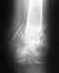

Здравствуйте! Меня зовут Наталья, мне 39лет, в апреле 2006г у меня был закрытый оскольчатый перелом средней трети левой бедренной кости со смещением. Был произведен остеосинтез титановым штифтом 19.04.06.Заключение на 03.09.09 - замедленный консолидирующий оскольчатый перелом. Регионарный остеопороз нижнй трети бедренной кости. Артроз тазобедренного и коленного суставов 1-2 ст. Постоянные боли в бедре.1. Можно ли удалить частично металлоконструкции для стимуляции остегенеза в месте перелома?(Мой рост - 156, вес -39. Анализ крови (ед.СИ): гемогл - 90, эритроц - 2,8, цвет.роказат - 0,90, СОИ - 30, анизоцитоз +, пойкилоцитоз +, полихроматофилия - гипохр.умерен)Мне отказано МСЭК в продлени инвалидности, мотивируя тем, что перелом сросшийся.2. Можно ли считать, что перелом сросся?

Если рентгенограммы свежие, то на них сращения нет.

Действительно, статический винт нужно было давно удалить. Хотя на сегодня вполне выглядит обоснованно более объемное вмешательство - замена стержня с рассверливанием на больший по диаметру. Еще и с латеральным изгибом лучше, поскольку точка входа уже есть через большой вертел.